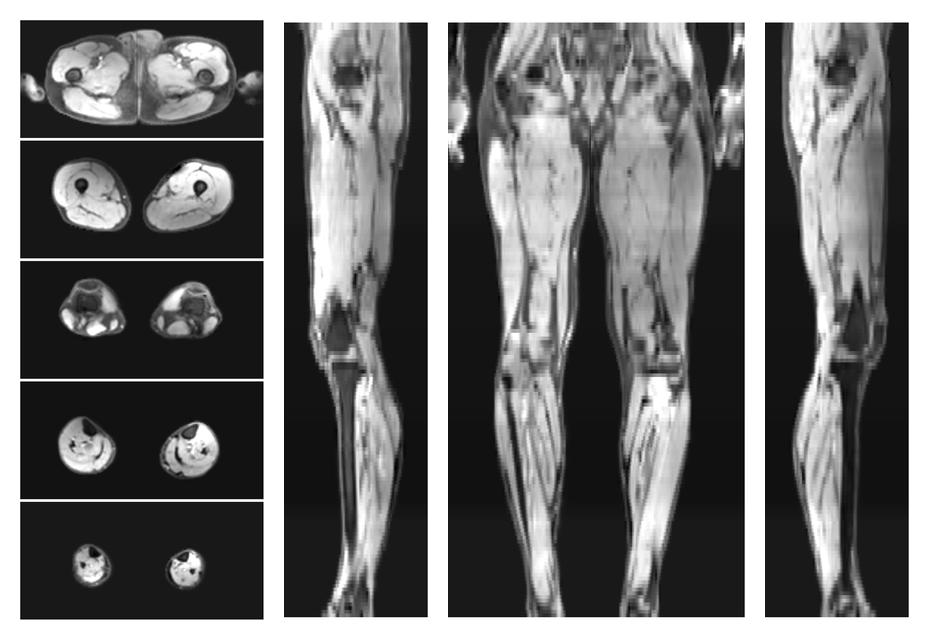

• Water only signal

The water part of the acquired multi-echo spin echo data.